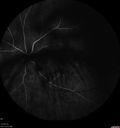

74 year old man with diabetes for about 40 years. No previous problems or treatments: EXTENDED HPI: Starting a little less then a week ago he woke up with something in the left eye. He saw a big blob in his vision. Since it started it is not getting better (also not getting any worse). The right eye is OK. This has not happened before. He is on ASA and Clopidogrel. VA OD: sc20/20+2 NscJ7-1 VA OS: sc20/63-2 NscJ2

Vitreous Hemorrhage with no evidence of PDR in the left eye443 views74 year old man with vision loss OS for about a week. The FA shows no PDR in the left eye but the right eye has very mild NVD. Diabetes for 40 years now on insulin.00000